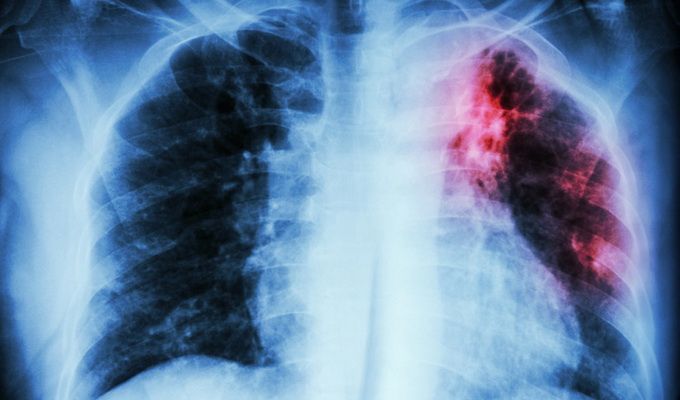

Современная классификация туберкулеза в основном базируется на принципах сопоставления жалоб пациента, клинических симптомов и признаков заболевания на рентгенографических снимках.

Современные принципы рентгенографической классификации

Достижения в рентгенографической диагностике туберкулеза, детальное патоморфологическое описание его форм в сочетании с предложенными Г.Р. Рубинштейном принципами классификации туберкулеза позволили на V Всесоюзном съезде фтизиатров принять клиническую группировку туберкулеза с включением нелегочных форм.

Она и явилась прообразом современной классификации, которая действует до настоящего времени. Эта классификация отражает главные критерии туберкулезного процесса в любых органах и включает основные клинические формы с характеристикой туберкулезного процесса, его локализацией, протяженностью, фазой и бактериовыделением, а также включает в себя возможные осложнения туберкулеза и остаточные изменения после его излечения.

Ниже приведена полная, существующая в настоящее время клиническая классификация туберкулезного процесса. Согласно Приложению к Приказу Минздрава России от 21.03.2003 № 2 в основу клинической классификации туберкулеза положено несколько принципов. Это:

- симптоматические рентгенологические особенности туберкулезного процесса (расположение и распространенность);

- его течение (фазы);

- наличие бактериовыделения.